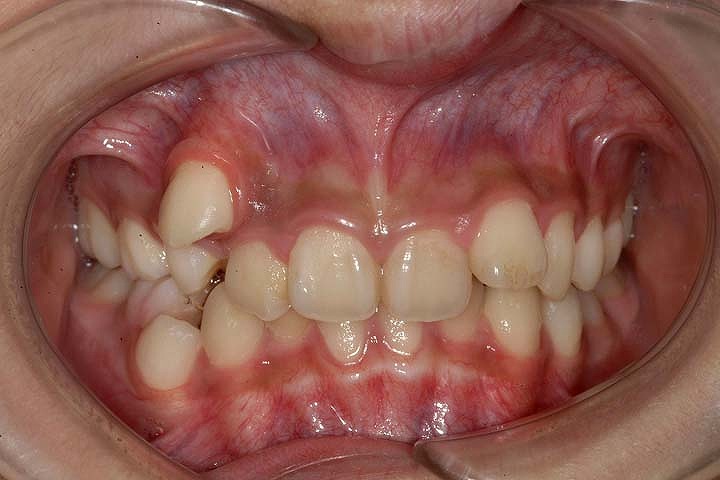

叢生(乱ぐい歯)

過蓋咬合(深いかみ合わせ)

歯のデコボコを主訴に来院された小学校5年生の患者さんです。叢生の程度は比較的重度でしたが、上顎第二大臼歯の萌出前であったので、ヘッドギアーとGMDを用い、大臼歯の後方への拡大を行いました。その後、その空隙を利用して、非抜歯でエッジワイズ装置を用いて配列を行いました。拡大処置1年6ヶ月、後期2年で治療いたしております。